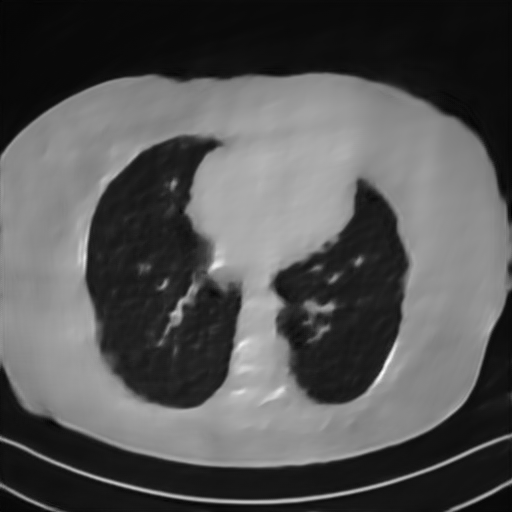

Fig. 4 presents the reconstruction results and residual images obtained by different methods for limited-angle reconstruction. As can be seen, the learning-based methods outperform the direct method and TV model, which exhibit serious artifacts in the missing angle region. Although the denoiser introduced by the FBP-Unet can somehow deal with the noises, the result still presents obvious artifacts. Compared to the SIPID, PD-net and FSR-nets, our LRIP-net1/2 can better preserve the image details and edges with less information left in the residual images. Thus, both the quantitative and qualitative results confirm that the low-to-high double-resolution strategy can improve the reconstruction accuracy for the limited-angle reconstruction problem.

We observe that the low-resolution image prior plays an important role in our method. More specifically, we compare the results of our LRIP-net with respect to different low-resolution priors, which are obtained by down-sampling rate of 1/2, 1/4, and 1/8, respectively. As can be seen in Table III, the best reconstruction results are obtained with the image prior reconstructed by the down-sampling rate of for 150∘, 120∘ and 90∘ limited-angle reconstruction. The visual comparison based on different image priors are also provided in Fig. 5, where obviously less artifacts are left in the reconstruction image by LRIP-net1/8. By comparing the running time, it is easy to see that the smaller the low-resolution image prior, the faster the LRIP-net works.